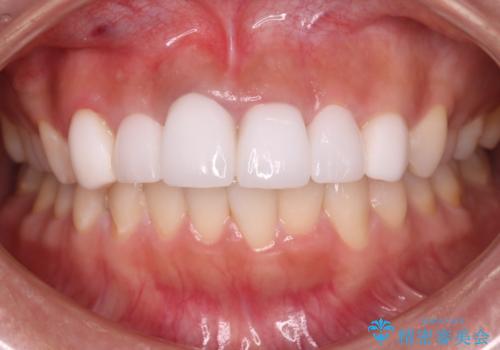

清掃性も上がったおかげで、歯肉の状態も良好に保てています。

色の調和もとれたので非常に満足いただけました。